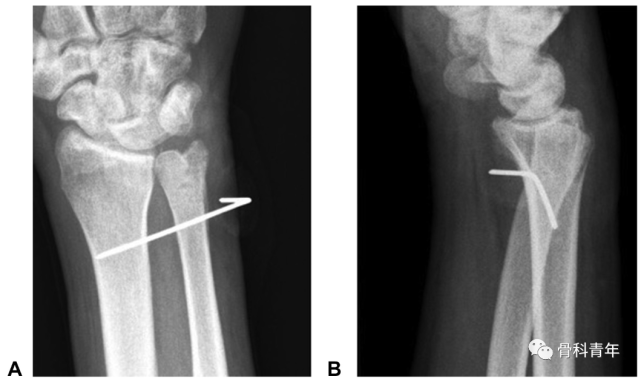

下尺桡关节脱位(distal radioulnar joint dislocation)

下尺桡关节脱位图片

下尺桡关节分离图片

下尺桡关节脱位